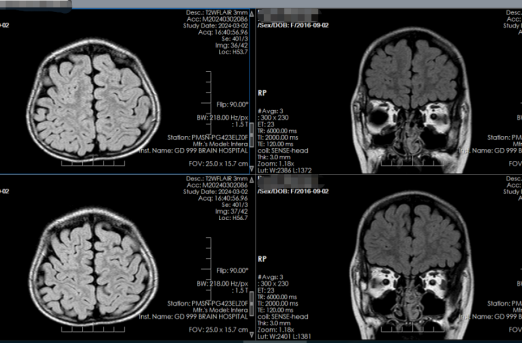

图4 头部MR检查:右侧额叶局部皮层略显增厚

完善脑电图、头部MR平扫检查后,证实患儿为眼睑肌阵挛癫痫,发作时伴面前摆手动作,且患儿的发作具有光敏感特点,即见光容易发作。结合症状,李花向家属详细解释了相关检查结果。